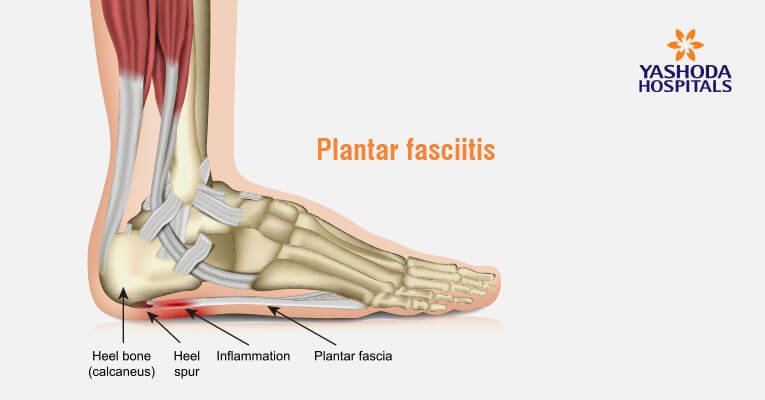

Heel Pain Causes Symptoms Diagnosis Prevention and Treatments